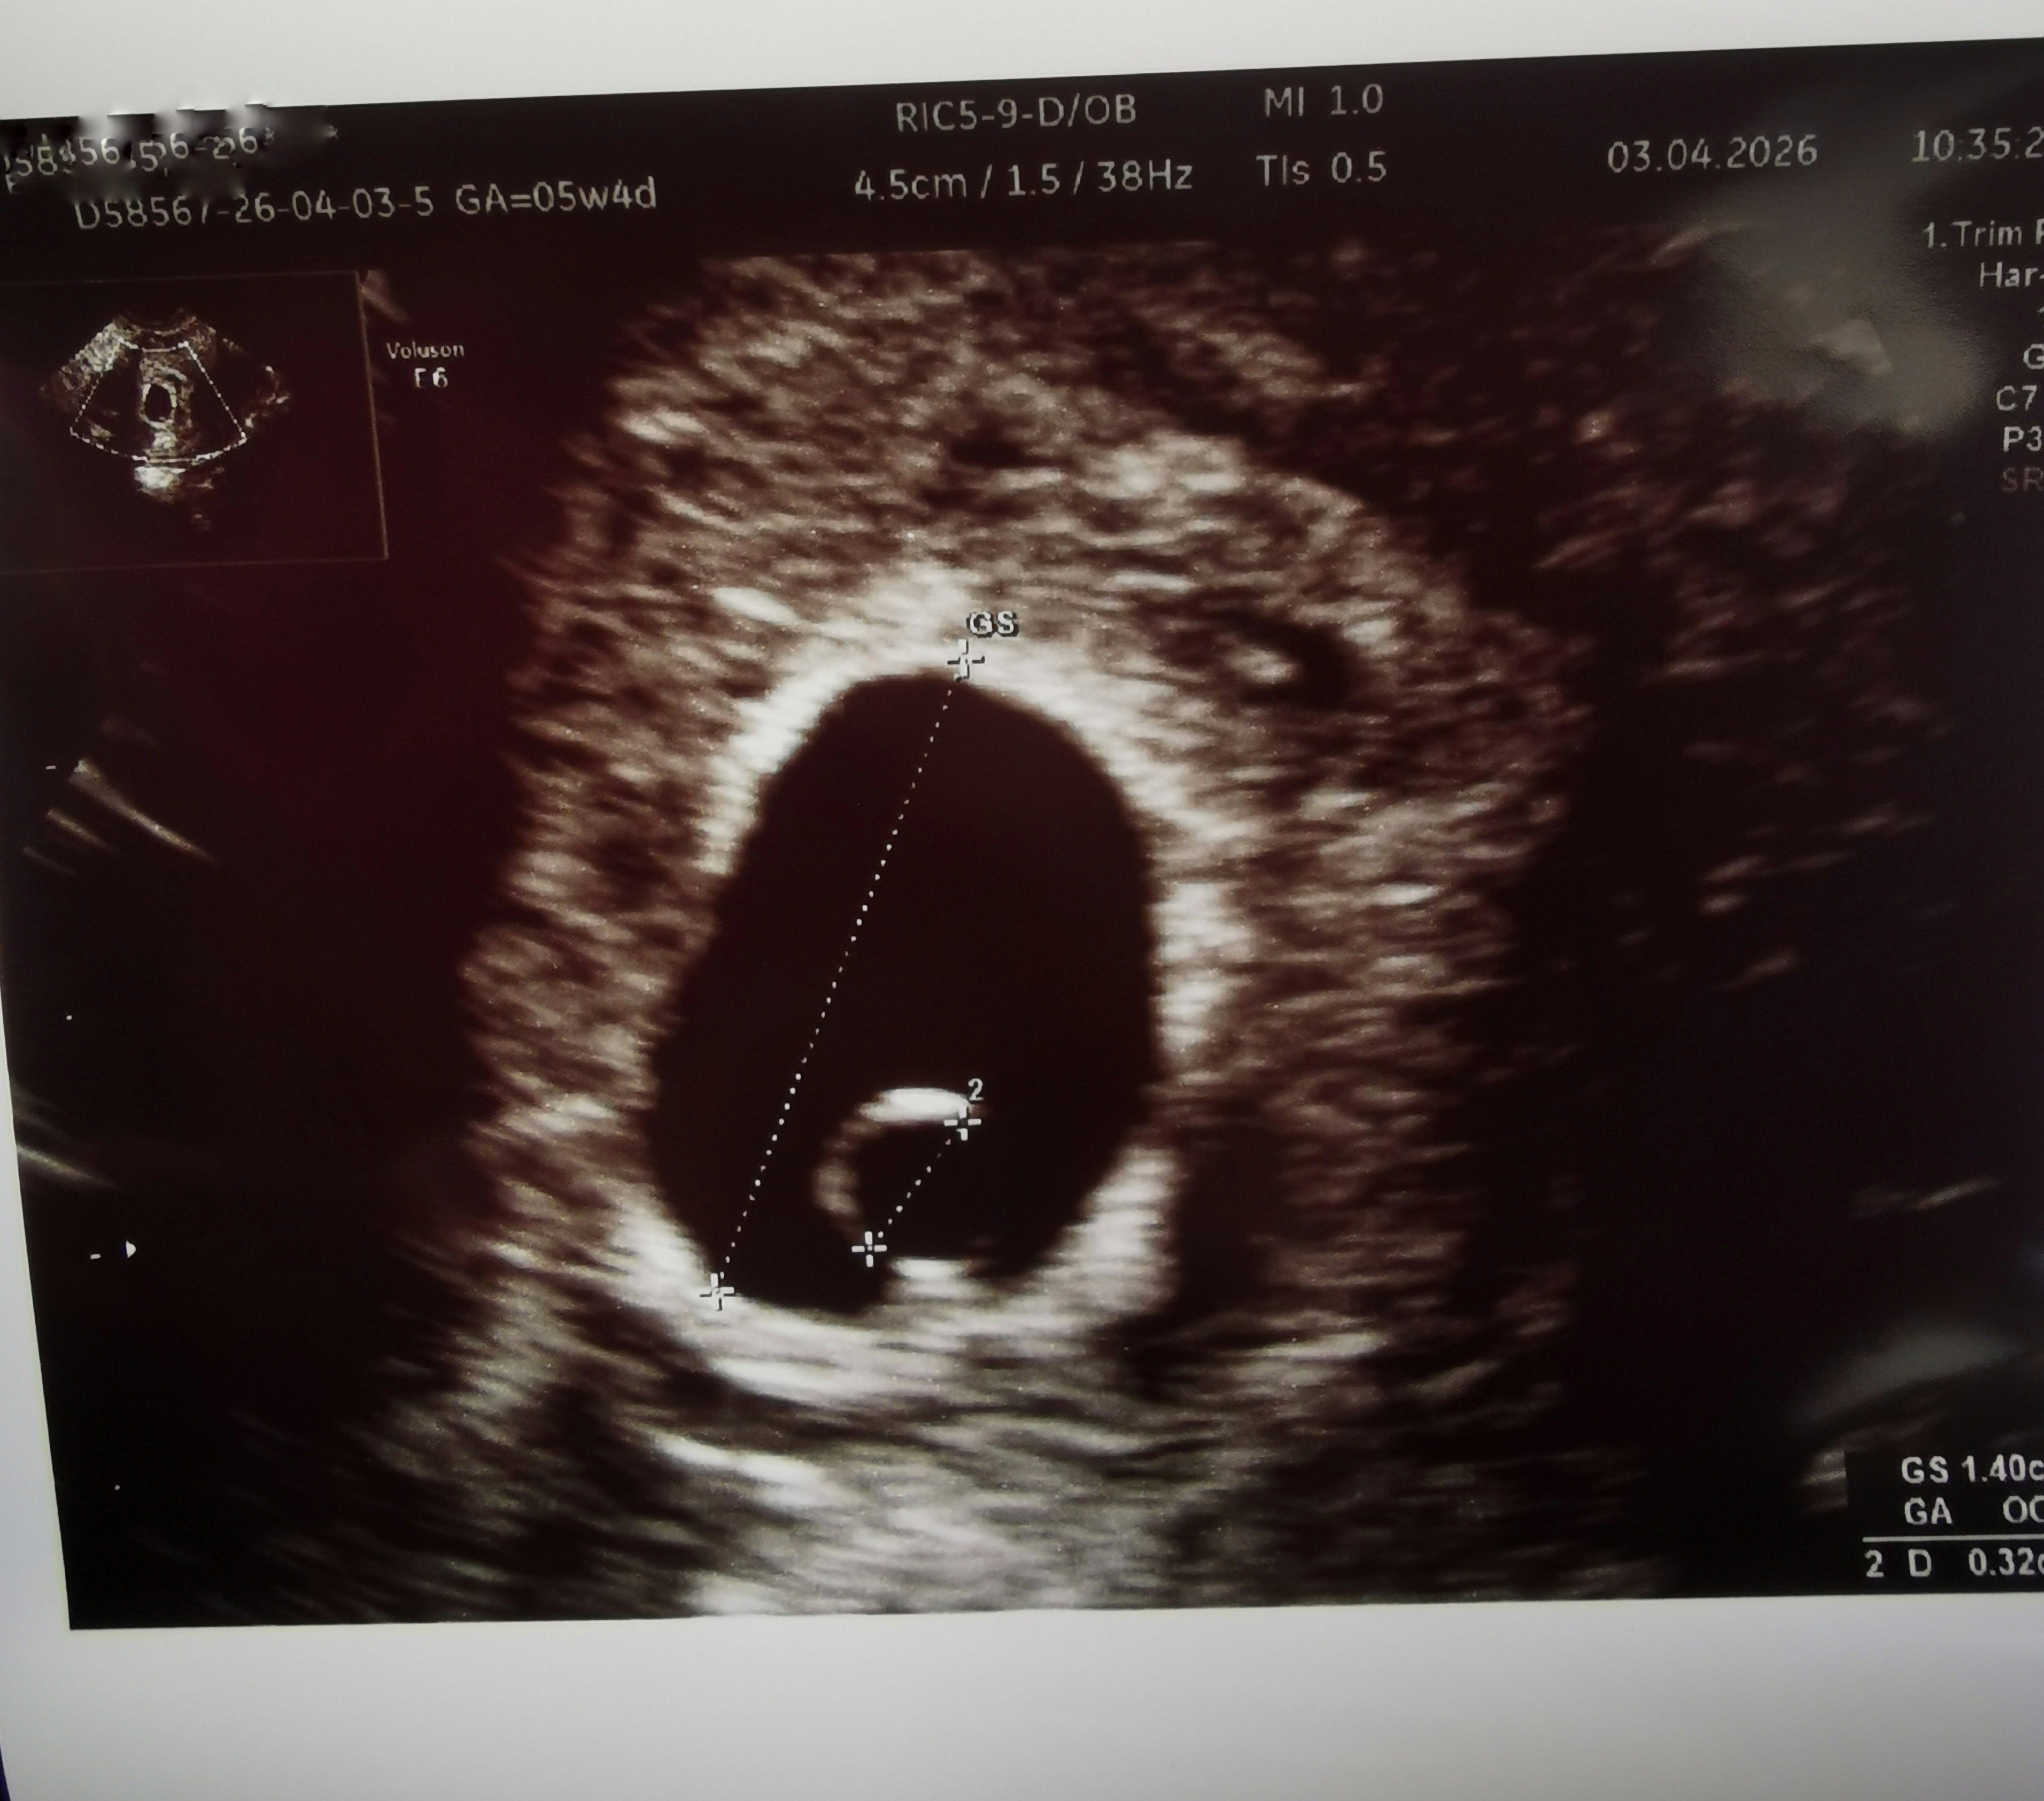

ja byłam na kolejnym usg dziś żeby sprawdzić czy pokaże się zarodek, powiem szczerze że ostatnie wiadomości tu na forum źle wpływają na moją psychikę i musiałam iść sprawdzić czy jest wszystko okej dla mojej głowy

I mamy malutki zarodek z bijącym serduszkiem

tak się cieszę! Dziś 5+5 tc